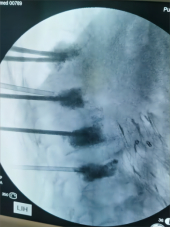

7. 复杂脊柱骨折内固定技术

随着区域内社会经济开发,复杂严重脊柱脊髓损伤病例增加,如何良好的手术治疗解除脊髓压迫、重建脊柱稳定性,使患者创伤最小、收益最大是促进患者康复至关重要的一环。皇冠娱乐城

已熟练开展各类脊柱损伤修复重建技术,每年完成复杂脊柱骨折手术处于区域领先水平。